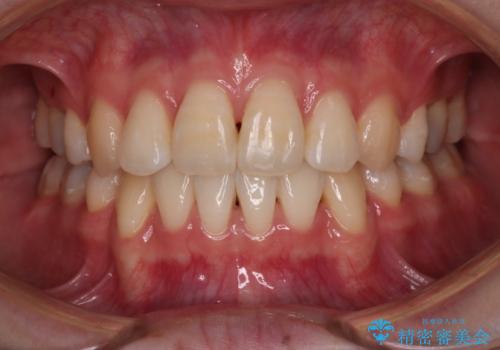

少しスペースクローズに時間がかかりましたが、MIを用いたワイヤー矯正で

主訴である出っ歯と叢生が改善されました。口も閉じやすくなり、スッキリとした口元になりました。